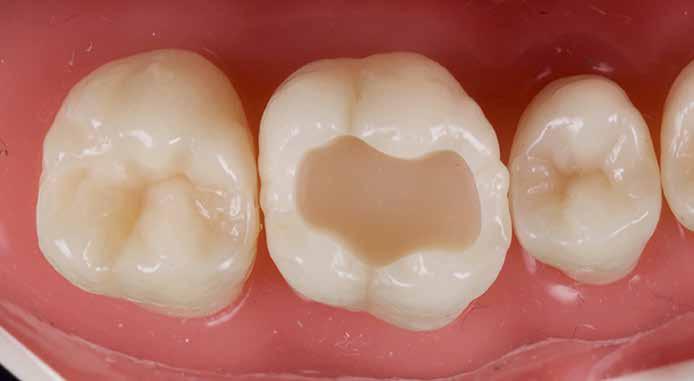

3. ábra: Rágófelszíni kavitás preparációja műfog modellen.

Kiindulópont: egyszerű I. osztályú rágófelszíni kavitás (3. ábra).